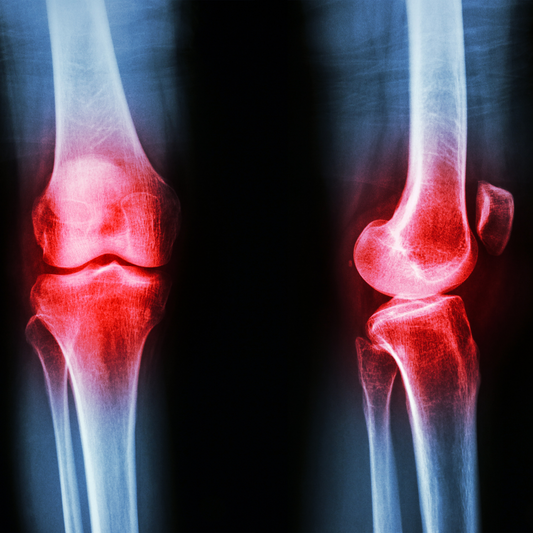

L’artrosi è una patologia degenerativa delle articolazioni che provoca dolore e rigidità. Scopri come l’osteopatia può aiutare a migliorare mobilità e qualità di vita.